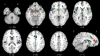

Results: Less gray matter in the high-risk group relative to controls was observed in anterior cingulate regions, left amygdala, and right insula. Lower gray matter volumes in FES compared with controls were also found in the anterior cingulate and right insula but not the amygdala. Lower gray matter volumes in the chronic group were most extensive, incorporating similar regions to those found in FES and high-risk groups but extending to superior temporal gyri, thalamus, posterior cingulate, and parahippocampal gryus. Subtraction analysis revealed less frontotemporal, striatal, and cerebellar gray matter in FES than the high-risk group; the high-risk group had less gray matter in left subcallosal gyrus, left amygdala, and left inferior frontal gyrus compared with FES. Subtraction analysis confirmed lower gray matter volumes through ventral-dorsal anterior cingulate, right insula, left amygdala and thalamus in chronic schizophrenia relative to FES.

Conclusions: Frontotemporal brain structural abnormalities are evident in nonpsychotic individuals at high risk of developing schizophrenia. The present meta-analysis indicates that these gray matter abnormalities become more extensive through first-episode and chronic illness. Thus, schizophrenia appears to be a progressive cortico-striato-thalamic loop disorder.